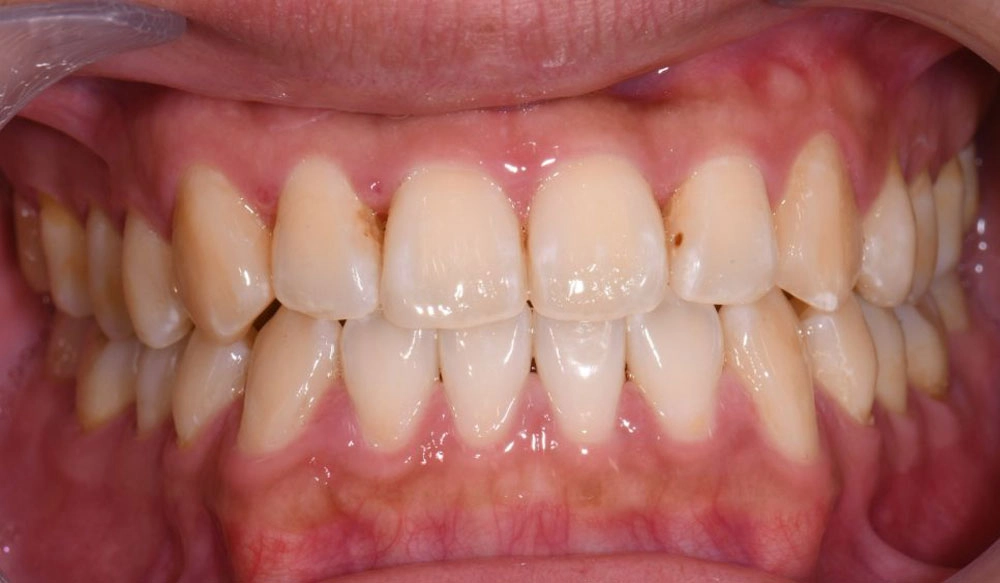

Extraction

Extraction is the removal of one or more teeth when a large amount of space needs to be created to align and create a correct occlusal relationship between the remaining teeth.

Patient Information:

Age: 16

Gender: Female

Invisalign Treatment Option: Invisalign Comprehensive

Total Treatment Time:

16 months